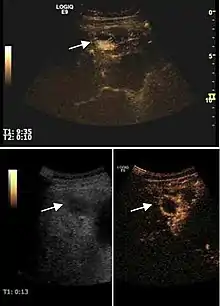

Hydatid liver cyst. Diagnostic criteria are the presence of membranes and sediment inside.